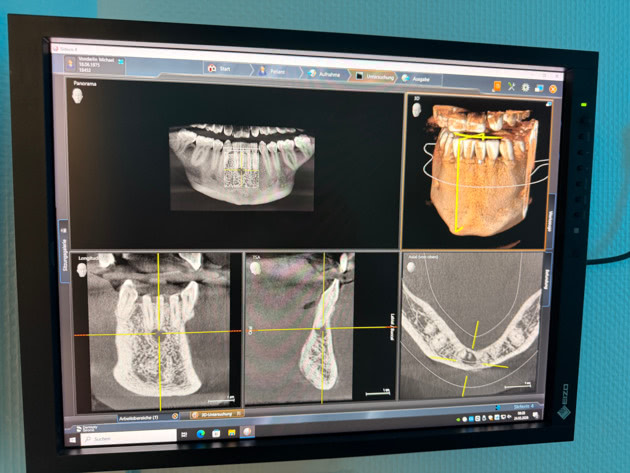

Damit Sie noch sicherer sein können und so wenig wie mögliche Risiken verbleiben, bieten wir modernste 3D-Röntgentechnik (DVT) an, mit dem sogar vor Behandlungsbeginn eine digitale Planung der Implantate vorgenommen werden kann.